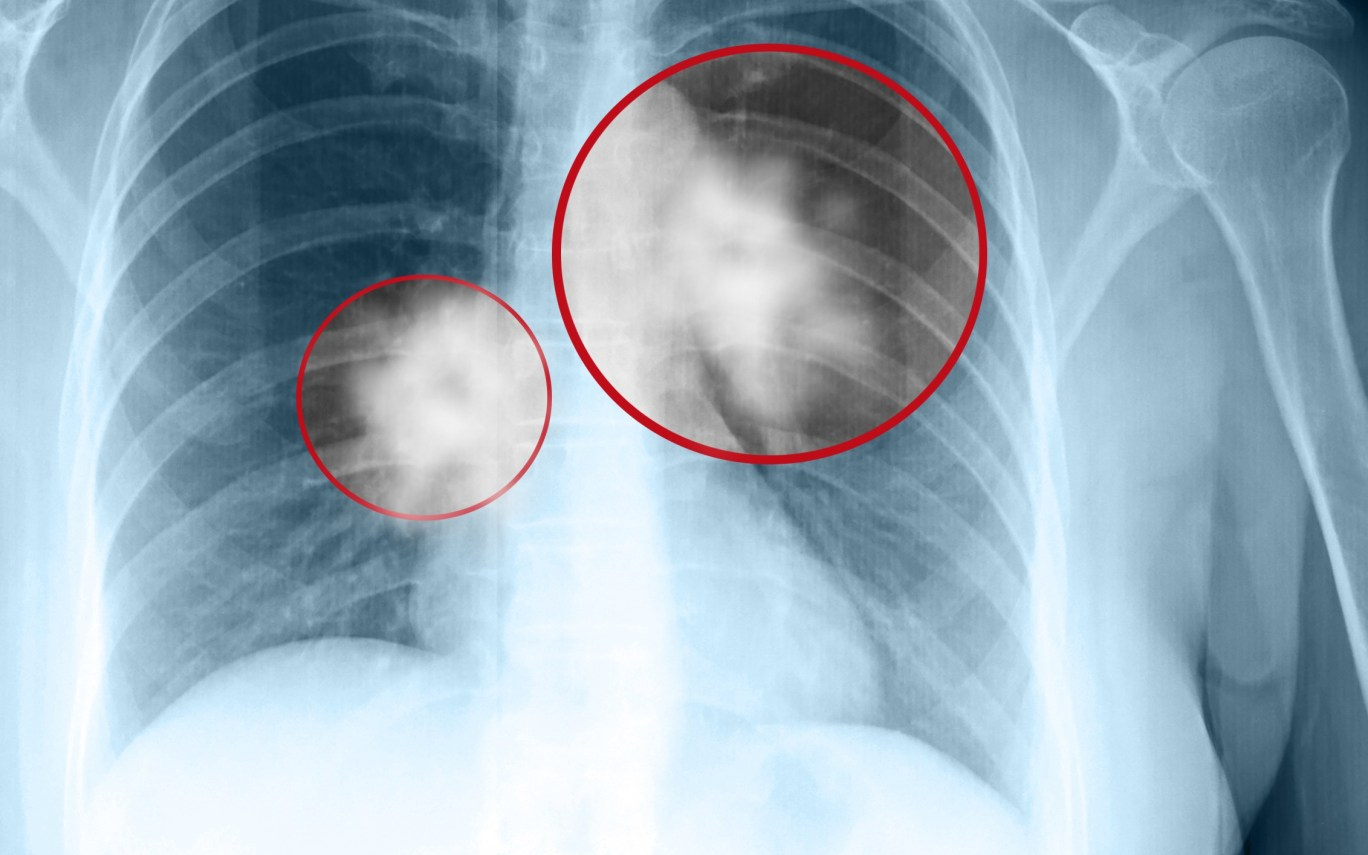

Nhiều người cho rằng không thể phát hiện sớm ung thư phổi. Thực tế, việc sàng lọc ung thư phổi bằng chụp cắt lớp vi tính đa dãy liều thấp (low-dose CT scan) đã được chứng minh là hiệu quả trong việc phát hiện các tổn thương nhỏ ở nhu mô phổi. Phương pháp này giúp giảm phơi nhiễm tia X và mang lại cơ hội điều trị sớm cho bệnh nhân.

Các đối tượng nguy cơ cao như người từ 55-74 tuổi, có tiền sử hút thuốc lá lâu năm hoặc đang hút thuốc đều nên thực hiện sàng lọc định kỳ. Tuy nhiên, các phương pháp khác như chụp X-quang, xét nghiệm đờm hay chỉ điểm ung thư trong máu chưa được chứng minh mang lại lợi ích trong việc giảm tỷ lệ tử vong do ung thư phổi.